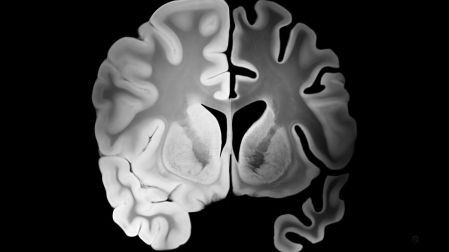

Un nuevo estudio podría predecir cuándo comienzan los síntomas del Alzheimer mediante análisis de sangre y biomarcadores cerebrales.

Un nuevo estudio podría predecir cuándo comienzan los síntomas del Alzheimer, una posibilidad que hasta hace poco parecía inalcanzable en la medicina. Anticipar el momento exacto en que la memoria empieza a desvanecerse ya no es solo una hipótesis.

Investigaciones publicadas en Nature, revelan que pruebas de sangre capaces de detectar biomarcadores del Alzheimer permiten estimar la edad promedio en la que podrían aparecer los primeros síntomas clínicos de la enfermedad.